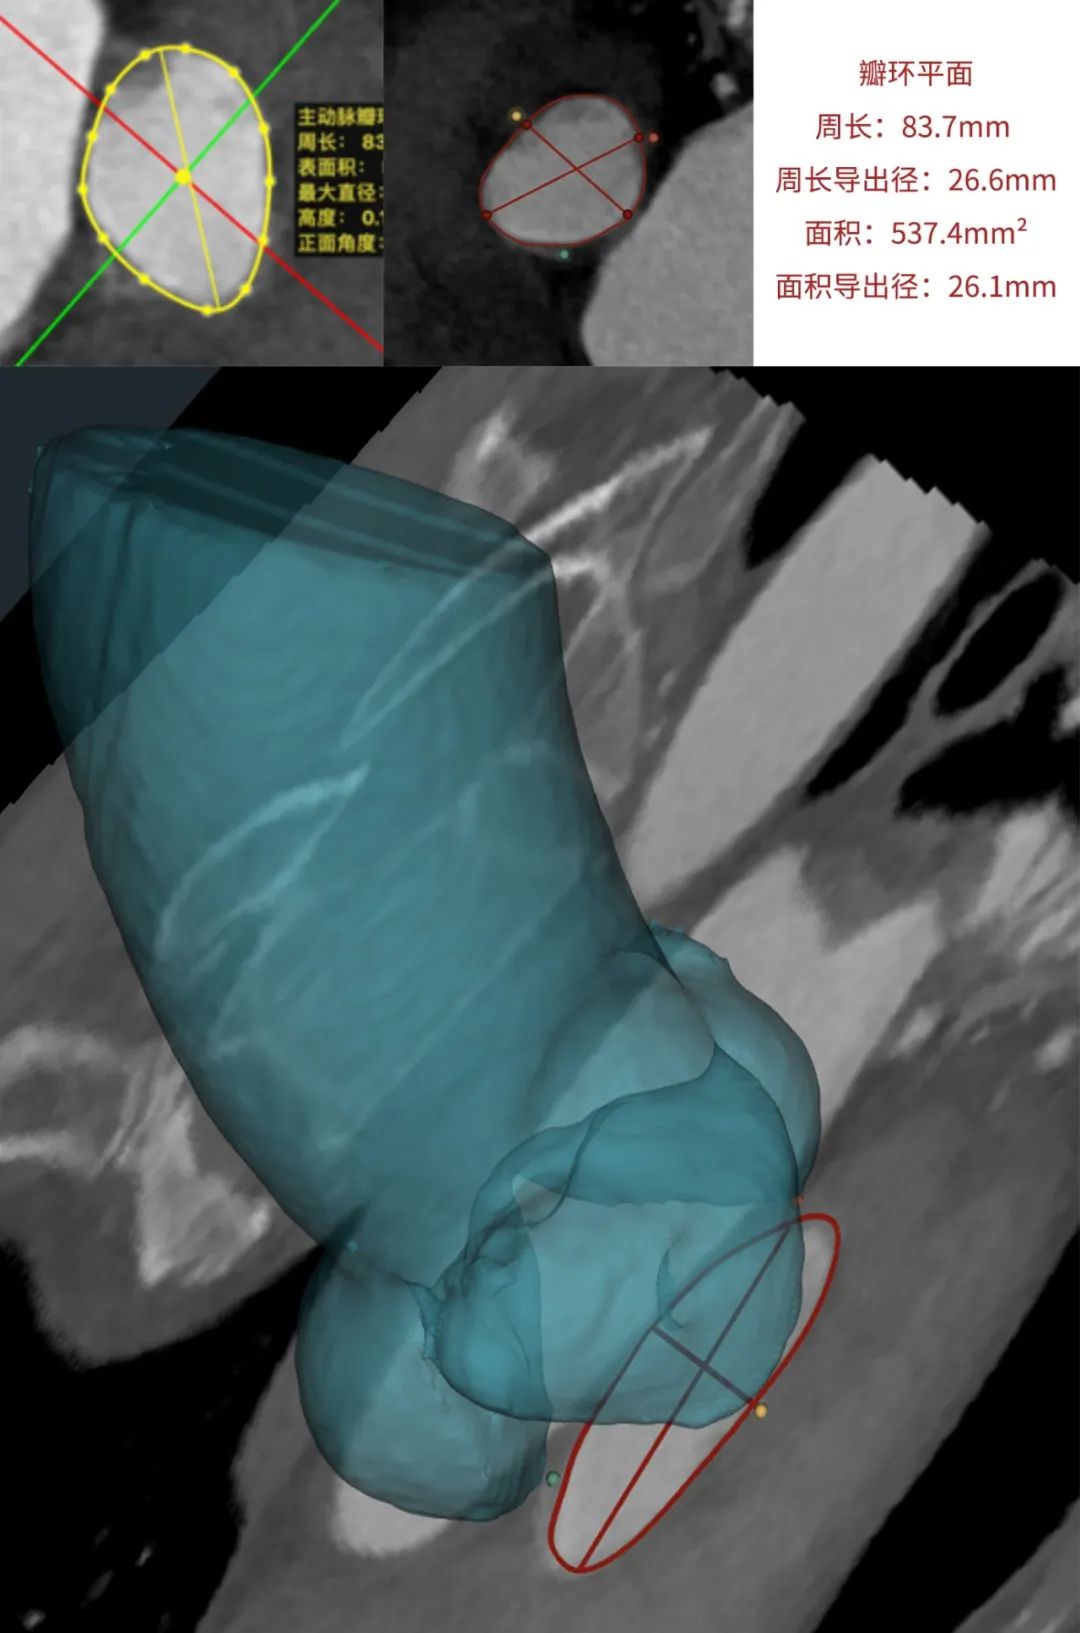

临床团队同时使用了基于医生手工描点的围术期影像评估软件和基于人工智能的瓣膜疾病围术期分析辅助决策软件进行术前影像学评估。

通过术前测量,对病例深入分析,结合人工智能术前分析辅助决策软件进行三维和二维图像融合,郭应强教授指出本例手术存在以下难点: